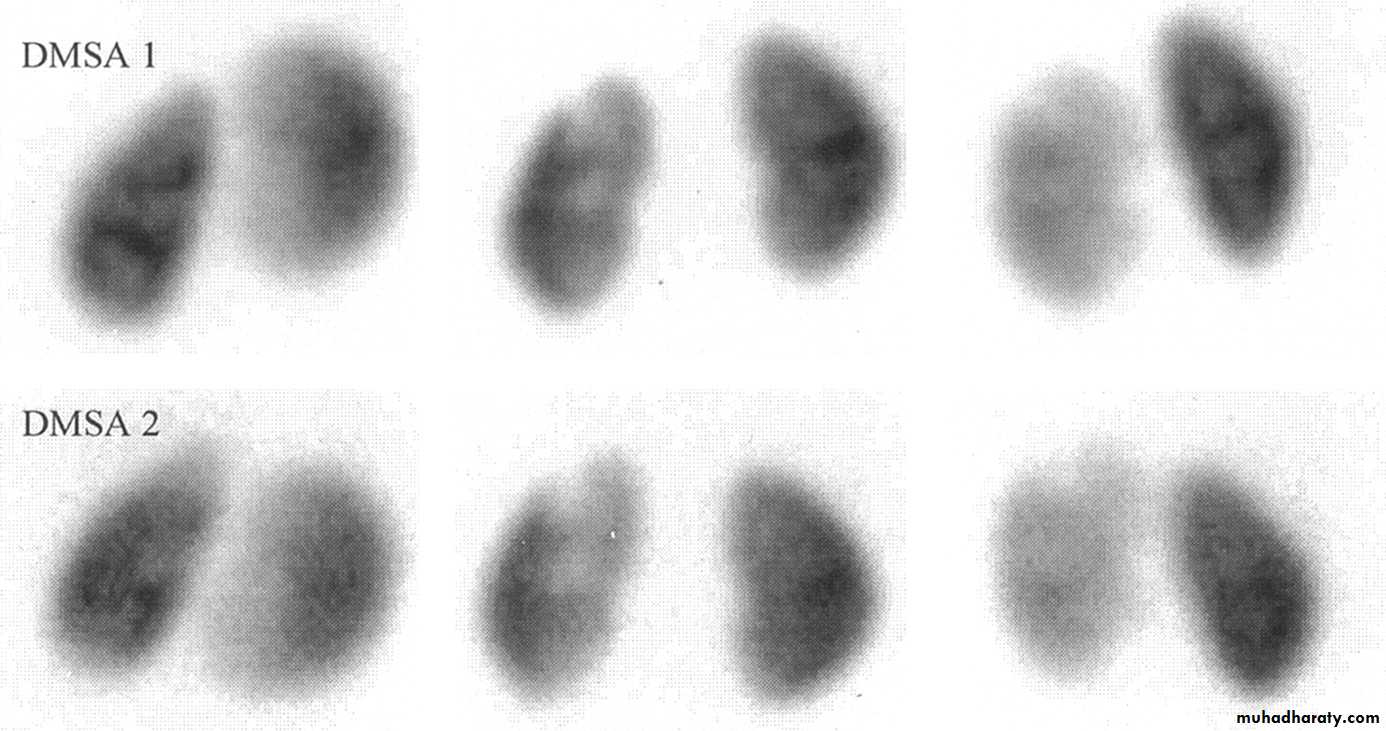

DMSA scan to detect and monitor associated renal cortical scarring.

Clinicians perform a dimercaptosuccinic acid scan (DMSA) to look for renal scarring at this juncture.

If the patient remains asymptomatic, urine cultures are obtained periodically (e.g., every 3 months) during treatment. US and radionuclide cystogram should be obtained at yearly intervals.